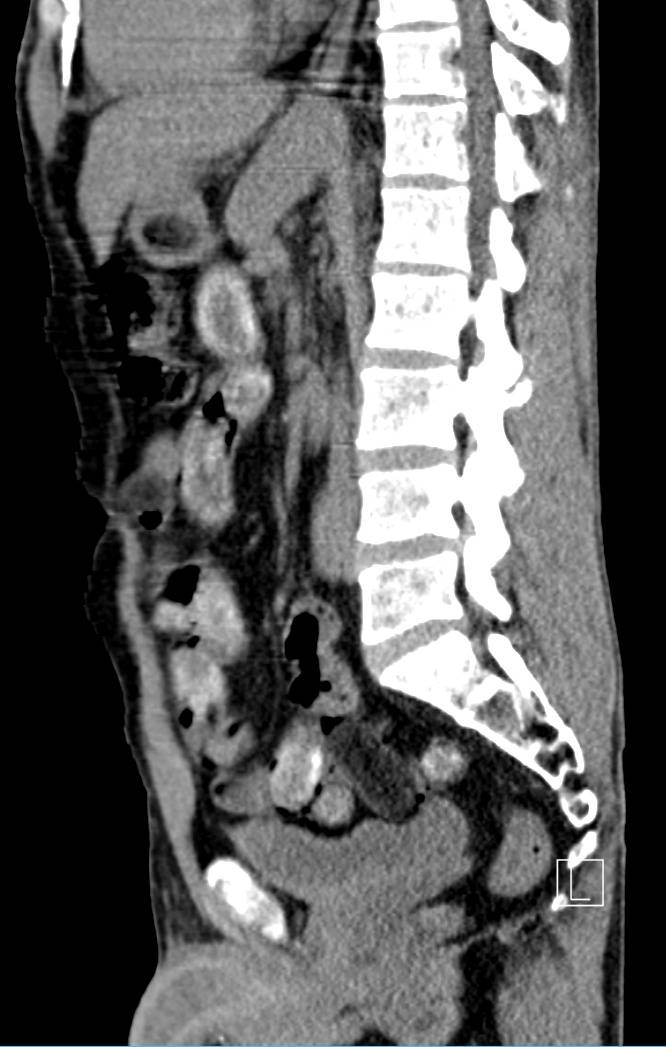

Nach der Kontrolle wurde der Mann zur weiteren Untersuchung ins Krankenhaus gebracht. Dort bestätigte ein Röntgenbild den Verdacht: Der Schmuggler hatte seinen Bauch mit insgesamt 75 sogenannten Bodypacks gefüllt. In den Drogenpäckchen befanden sich 450 Gramm Kokain und 300 Gramm Heroin - mit einem Straßenverkaufswert von fast 50.000 Euro.